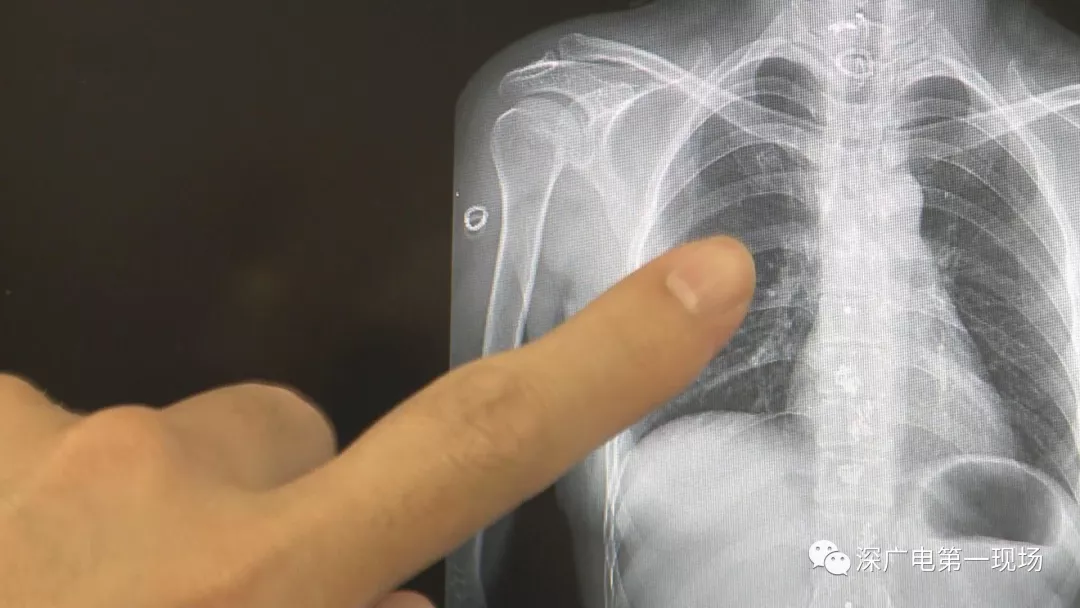

深圳一女子全身被植入彈簧圈,數(shù)量多到驚人!竟是為治這病…

經(jīng)醫(yī)院常規(guī)檢查后發(fā)現(xiàn)

為了治病

這位病人竟然在全身

被植入了大!量!彈!簧!

數(shù)量多到無(wú)!法!計(jì)!數(shù)!